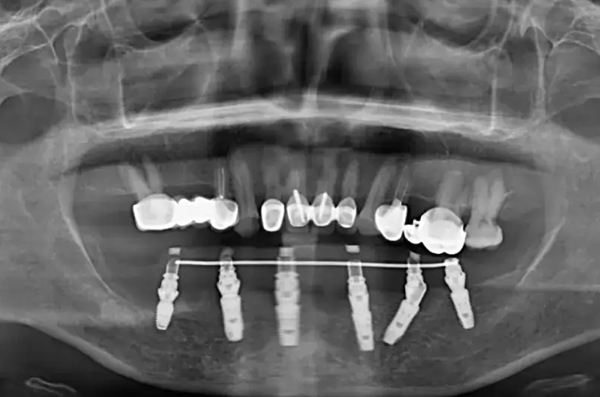

重慶齒齒美口腔醫(yī)院擁有豐富的種植牙成功病例,無論是單顆種植還是全口種植,齒齒美口腔都能提供有效的解決方案。

這些成功病例不僅證明了齒齒美口腔的技術(shù)實(shí)力,還為患者提供了寶貴的參考。患者可以通過查看這些成功病例,了解種植牙的成效和過程,增加對(duì)種植牙手術(shù)的信心。